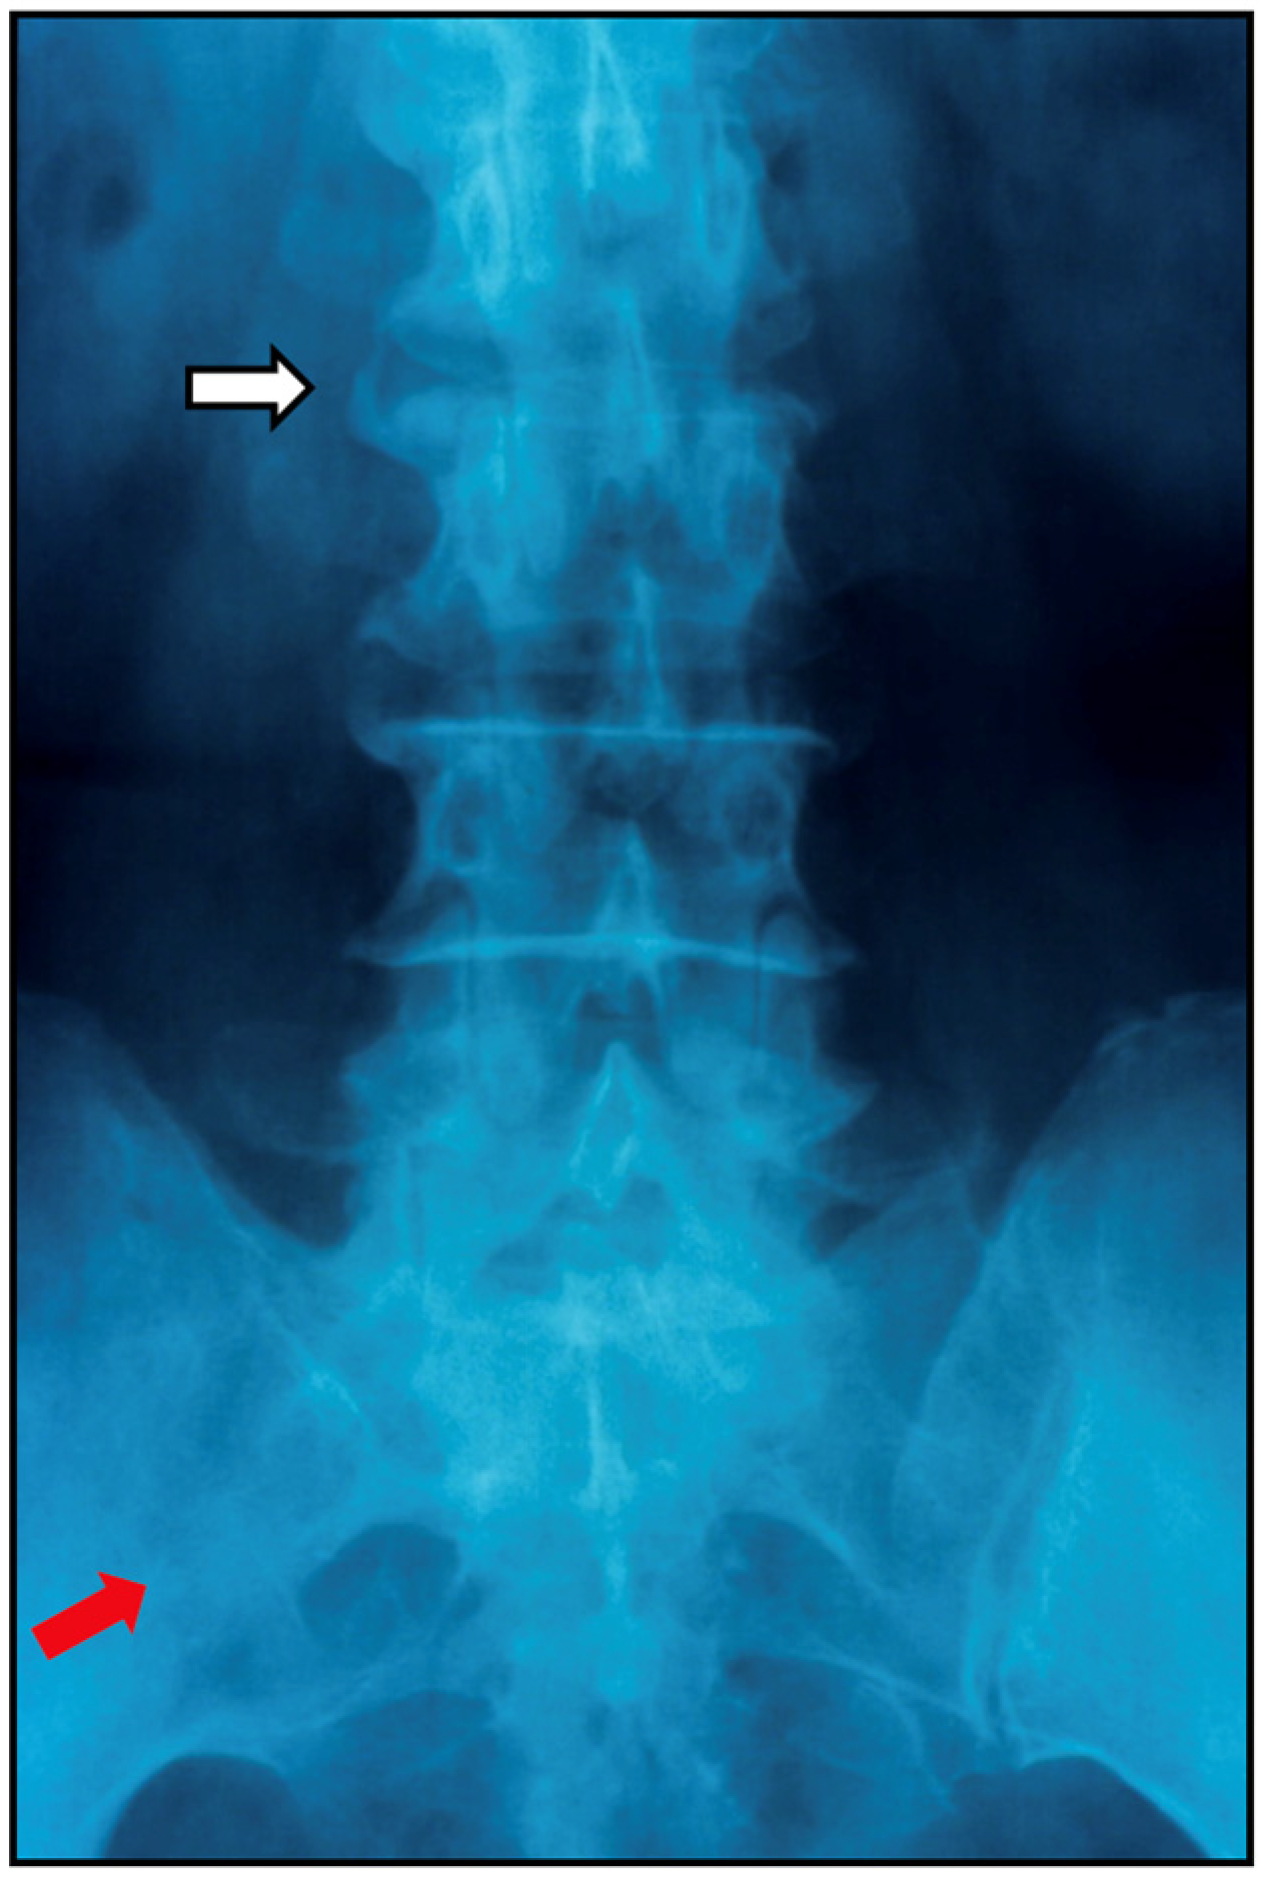

7.2.1. Plain Radiographs